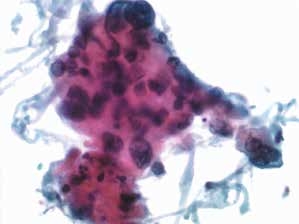

图4-67 非角化型鳞癌(高倍、液基、巴氏染色)

癌细胞成团排列,异型性明显,胞核增大深染,核仁可见,染色质粗颗粒状,胞质蓝染,肿瘤素质十分明显。